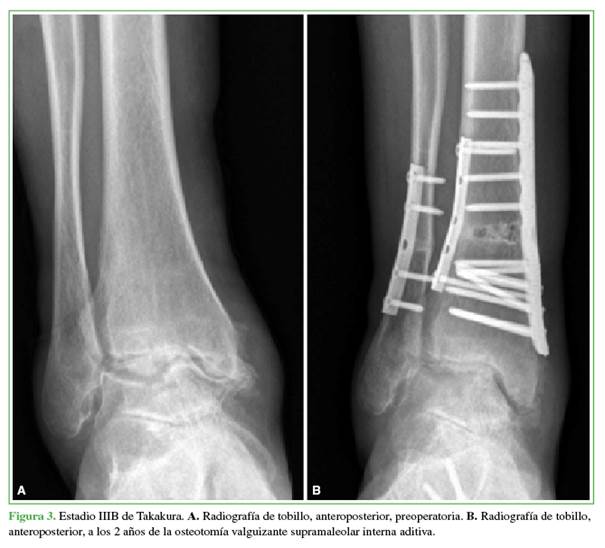

La artrosis se clasificó según la clasificación de Takakura-Anaka en la radiografía de frente con apoyo. Esta clasificación incluye cuatro estadios; I: no hay disminución del espacio articular, pero hay esclerosis subcondral del hueso y osteofitos; II: disminución del espacio articular medial o lateral; IIIA: obliteración del espacio medial o lateral; IIIB: obliteración del espacio medial o lateral que se extiende hasta el domo astragalino; IV: obliteración completa del espacio articular.18

Antes de la cirugía, seis (46,1%) practicaban actividad deportiva recreativa y todos ellos retornaron al deporte. En 12 (92,3%), se logró la consolidación radiográfica luego de la cirugía, en una mediana de 10.4 semanas (RIC 8-12) (Figuras 2 y 3). Se observó seudoartrosis en un paciente, por lo que requirió una cirugía de revisión. Se realizaron 25 procedimientos agregados (Tabla 2).